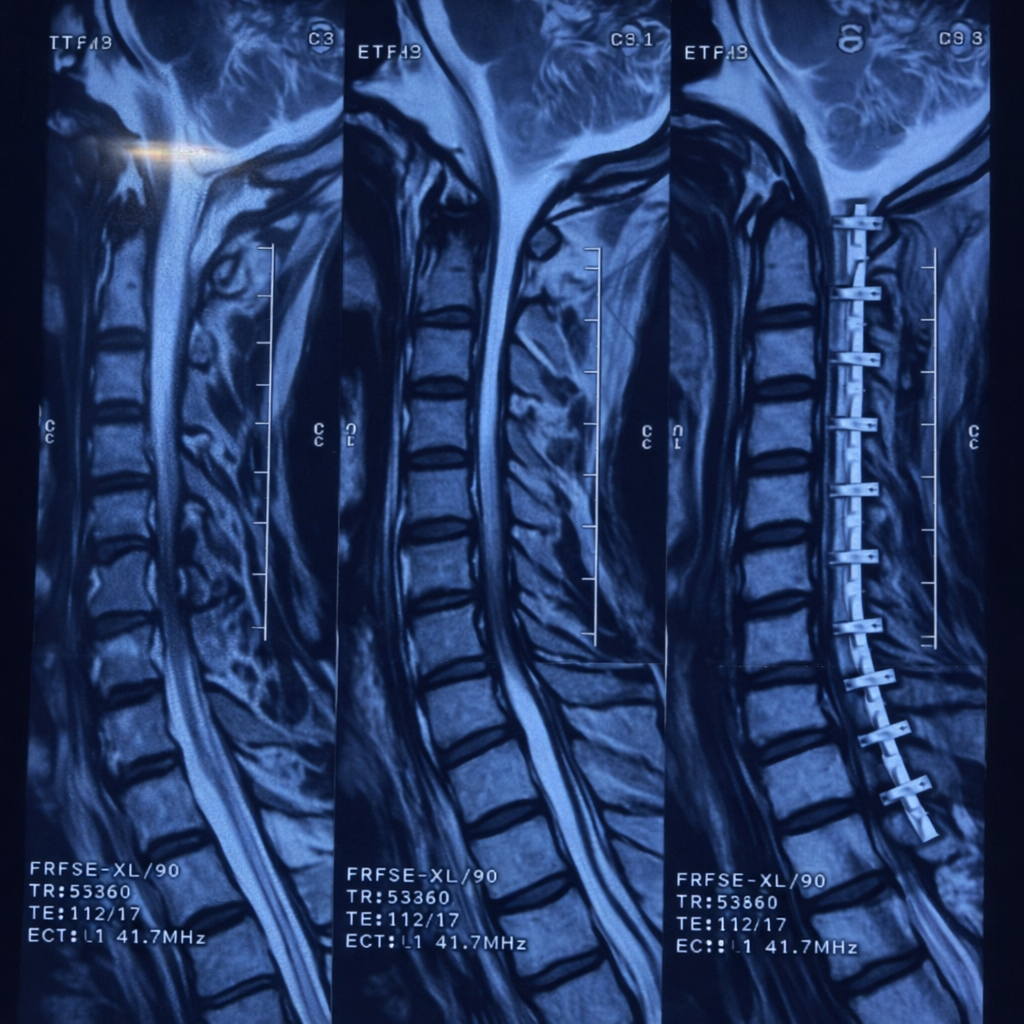

Delhi Sciatica Surgery Due to three fractures in the D9 and D10 vertebrae, a cirugía de columna vertebral was performed...